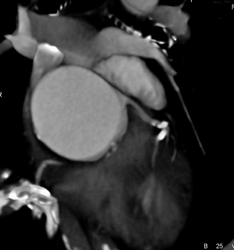

Pulmonary Stenosis